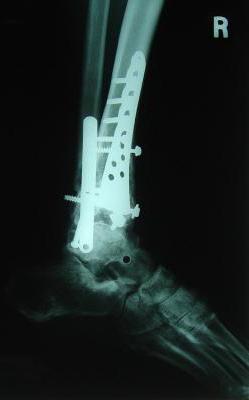

Post-corrective surgery X-Rays of the damaged right & left legs / ankles

The first two x-rays show Liam’s left ankle and pelvis prior to the accident. For comparison purposes it is interesting to see the

differences. The next x-rays were taken after the corrective surgery performed by Dr. Armendariz. Noticed that Dr. Armendariz has used tibia

bracing and also aligned the bone fragments of the left leg so that they could heal in the proper orientation. The external fixation has been

removed and Liam’s left foot has been returned to a more natural alignment.